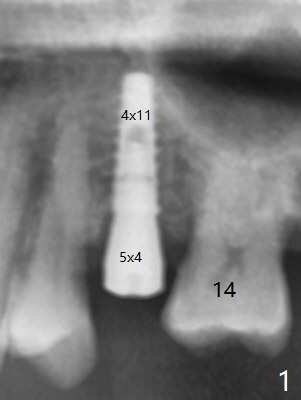

When a 4x11 mm FC is placed to the depth at #13, the palatal crestal bone is indistinct on probing. The implant is then placed ~ 1 mm deeper. To avoid contact between the future abutments and the mesiobucco-distal crest, a 5.5 mm profile drill is used. It appears that a 5x4 mm healing abutment has clearance from the crest (Fig.1,2 C). Immediate postop CT 3 D palatal view shows slight possible implant (Fig.3 I) thread exposure disto-palatal. To avoid this situation, the implant should have been designed more buccal (Fig.4 coronal section) because of the preexisting palatal defect (Fig.5,6) with low bone density palatocoronally (Fig.7). CT should have been taken prior to extraction. PRF or GEM21S should have been used. The patient will return for restoration (probably progressive loading) 3 months postop. In fact a pair abutment is placed 6 months postop (due to coronavirus, Fig.8). There is crestal bone palatal to the implant 6.5 months postop (Fig.9).